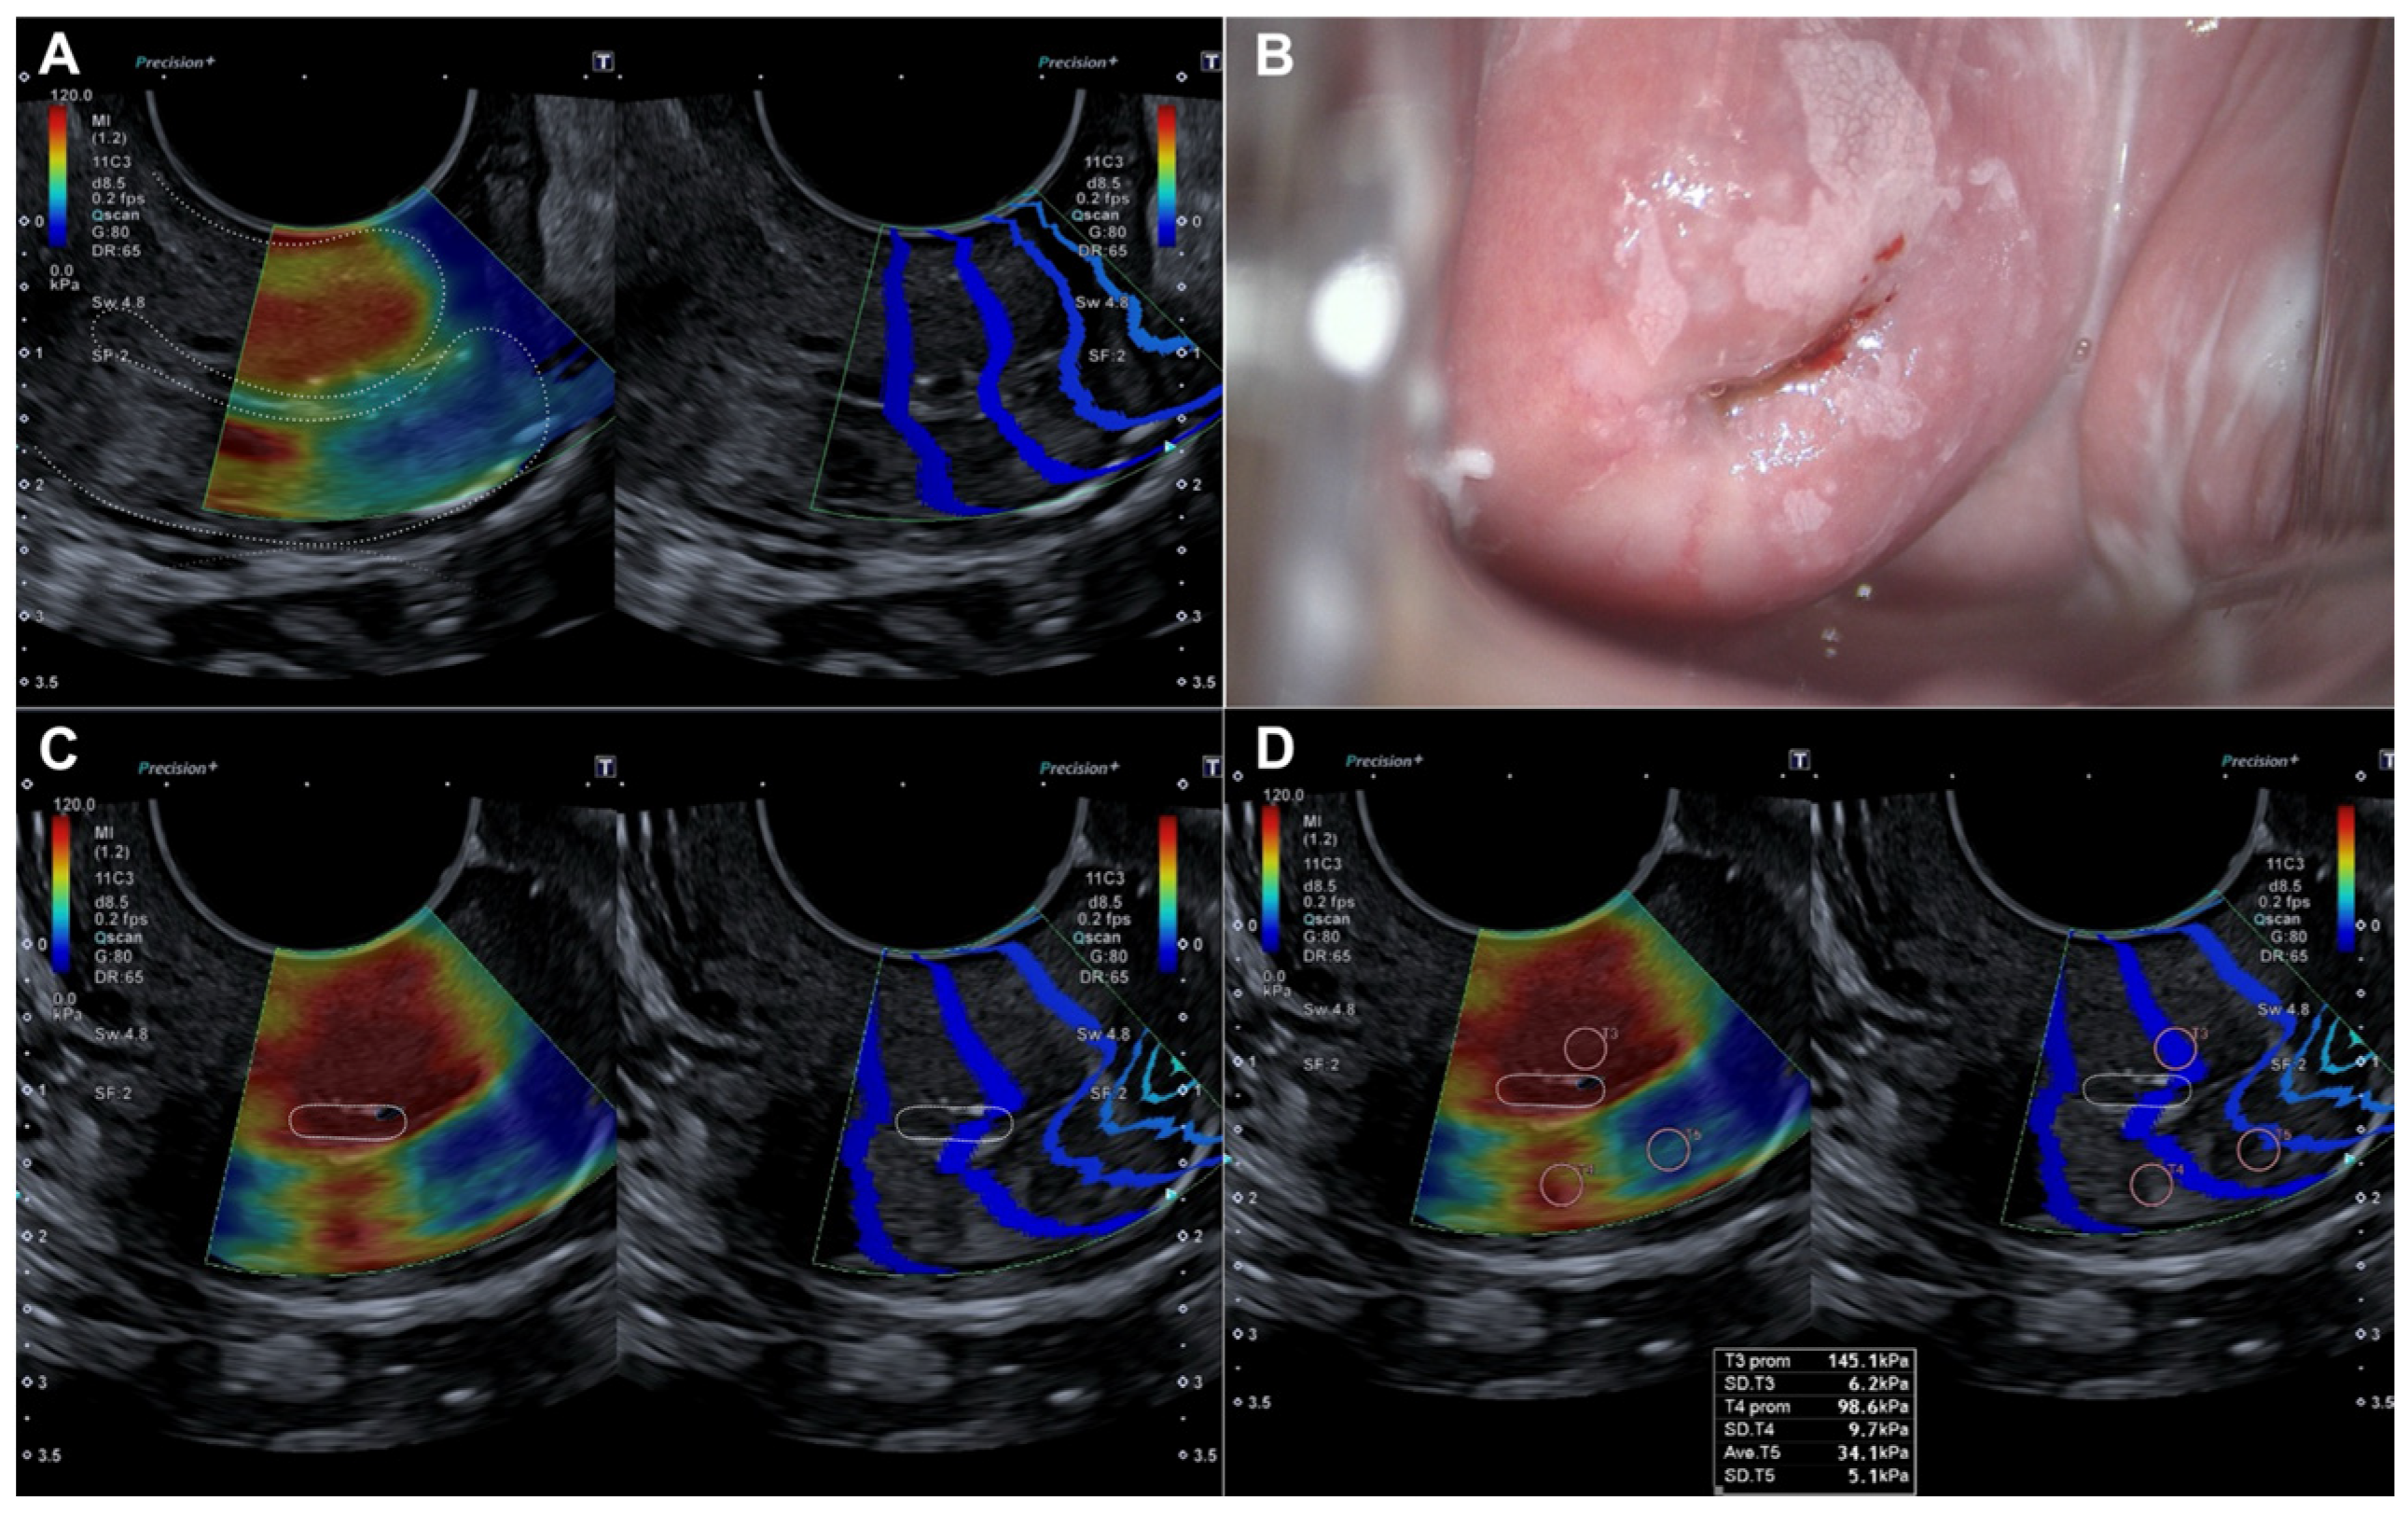

Histopathological evaluation of the 82 conization specimens, which were used as the gold standard, was performed to locate the lesion in the four quadrants of the cervix as previously divided. When comparing lesion localization in the histopathological study of the surgical sample with the localization shown by colposcopy and SEC, we observed a moderate agreement with colposcopy (0.456 (p < 0.05)) compared to a very good agreement with SEC (0.815 (p < 0.05)) (Table 4). Figure 3 illustrates how a dysplastic lesion is visualized in both the endocervix and exocervix, and compared with colposcopy.

Figure 3.

Evaluation by elastography (SonoElastoColposcopy) and colposcopy. (A) Longitudinal section of the uterine cervix (dotted line) showing an endocervical dysplastic lesion in red. (B) Colposcopic appearance of the dysplastic lesion of the ectocervix at 12 and 6 o’clock. (C) Cross-section of the ectocervix by SEC (dotted line) in red showing a dysplastic lesion of the ectocervix at 12 and 6 o’clock. (D) Cross-section of the ectocervix by SEC (dotted line) in red showing a dysplastic lesion of the ectocervix at 12 and 6 o’clock, with quantitative evaluation of the dysplastic lesion in KPa.